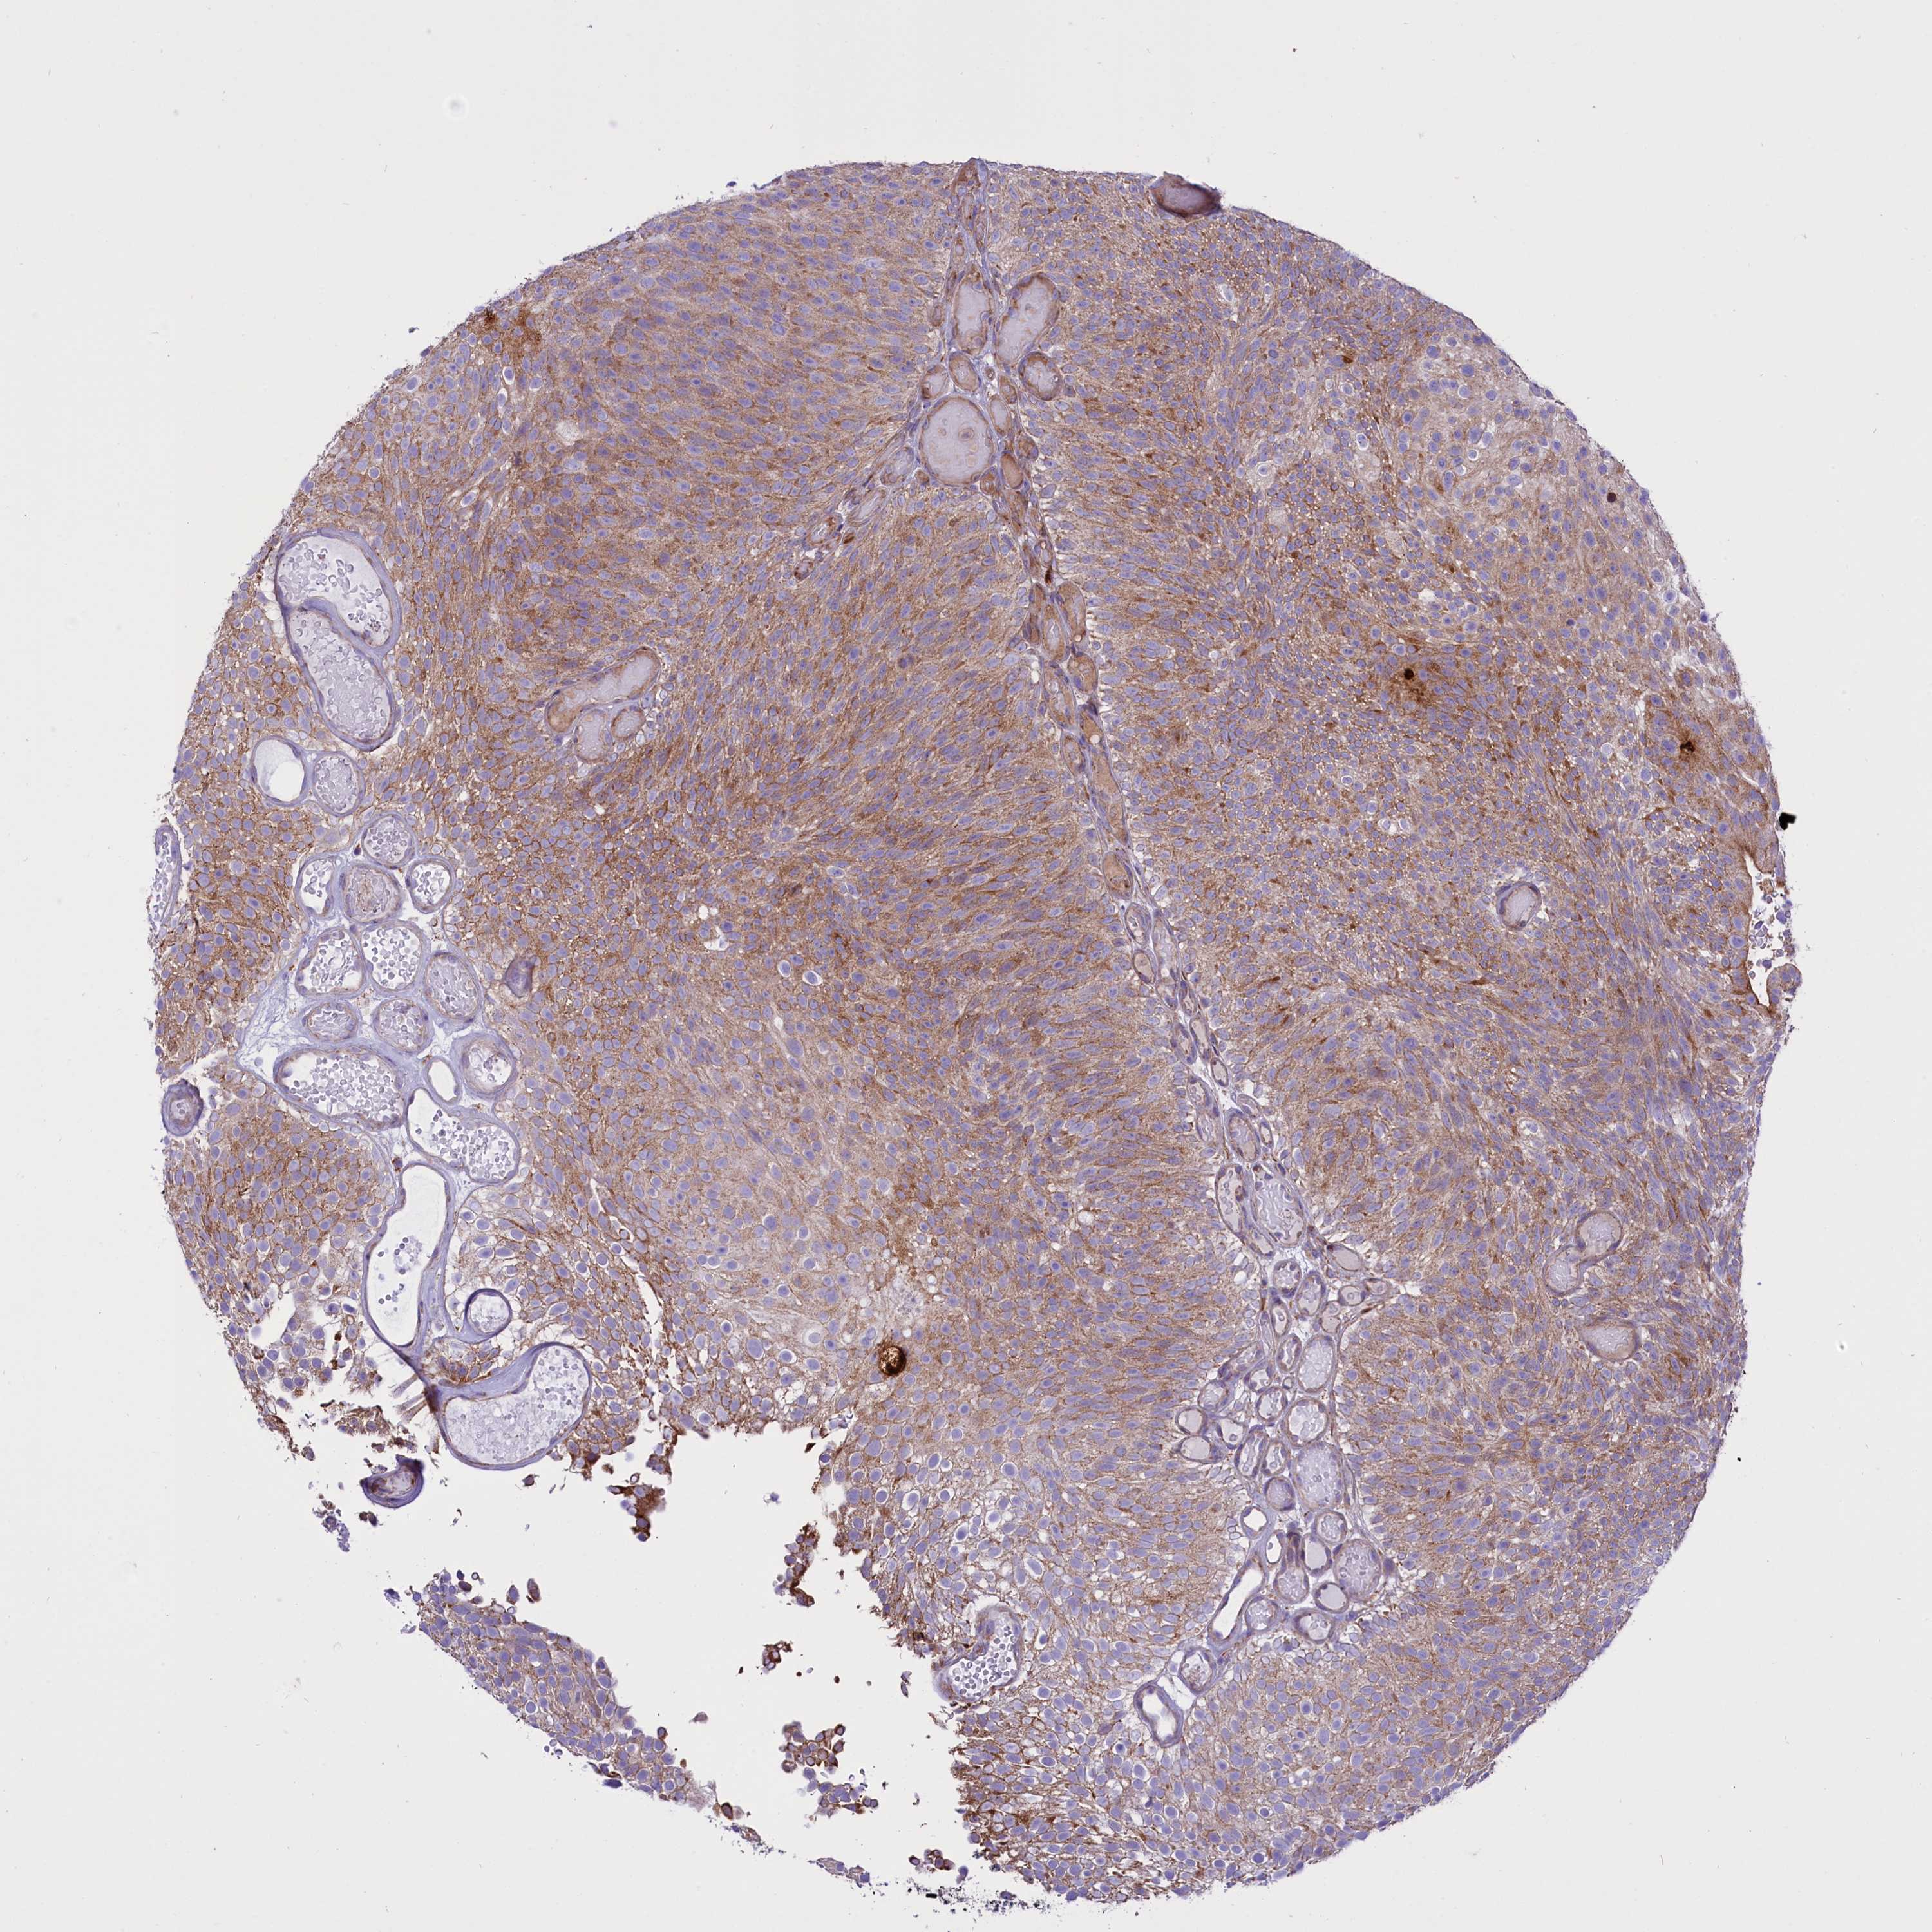

UROTHELIAL CANCER - Protein expressioni

A mouse-over function shows sample information and annotation data. Click on an image to view it in a full screen mode. Samples can be filtered based on level of antibody staining by selecting one or several of the following categories: high, medium, low and not detected. The assay and annotation is described here.

Antibody stainingi

Antibody staining in the annotated cell types in the current human tissue is reported as not detected, low, medium, or high, based on conventional immunohistochemistry profiling in selected tissues. This score is based on the combination of the staining intensity and fraction of stained cells.

Each image is clickable and will lead to virtual microscopy that enables deeper exploration of all samples and also displays staining intensity scores, fraction scores and subcellular localization as well as patient and tissue information for each sample.

Antibody HPA039832

Antibody CAB011476

Urothelial carcinoma, High grade

Urothelial carcinoma, Low grade